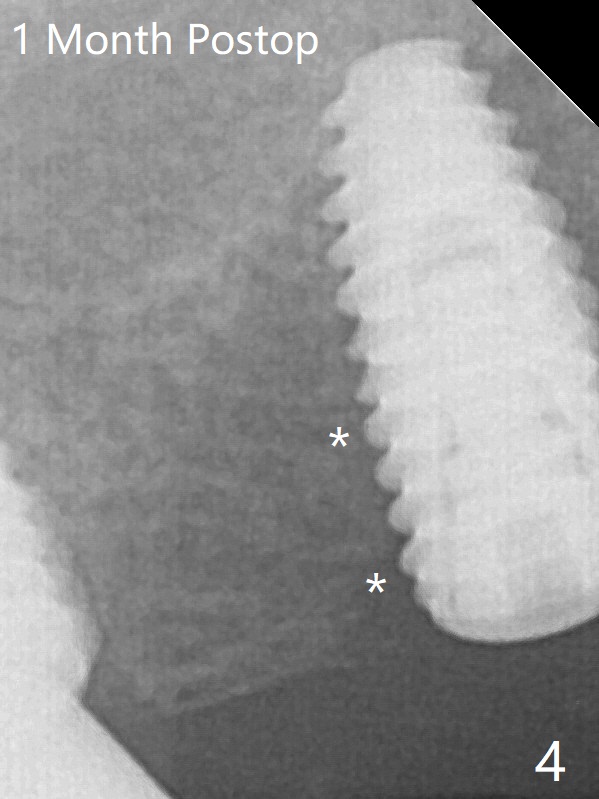

A 4.5x10 mm implant is placed at #3 subcrestal; the healing abutment is incompletely seated (Fig.2). One month postop, the implant is infected with distal bone loss (Fig.4). Bone graft is added. Bone loss seems to reduce 4 months post implant placement (Fig.6 *). Uncover is conducted at the site of #3; there is no superficial infection 7.5 months postop (Fig.8). There is a large buccal defect upon incision with dark hemorrhage. In fact the bone density is low crestally (Fig.8 *). Bone graft is placed for the 2nd time. Eleven months later (1.5 years post implant placement), the bone regrows crestal (Fig.9 *). 保险:愈合螺帽